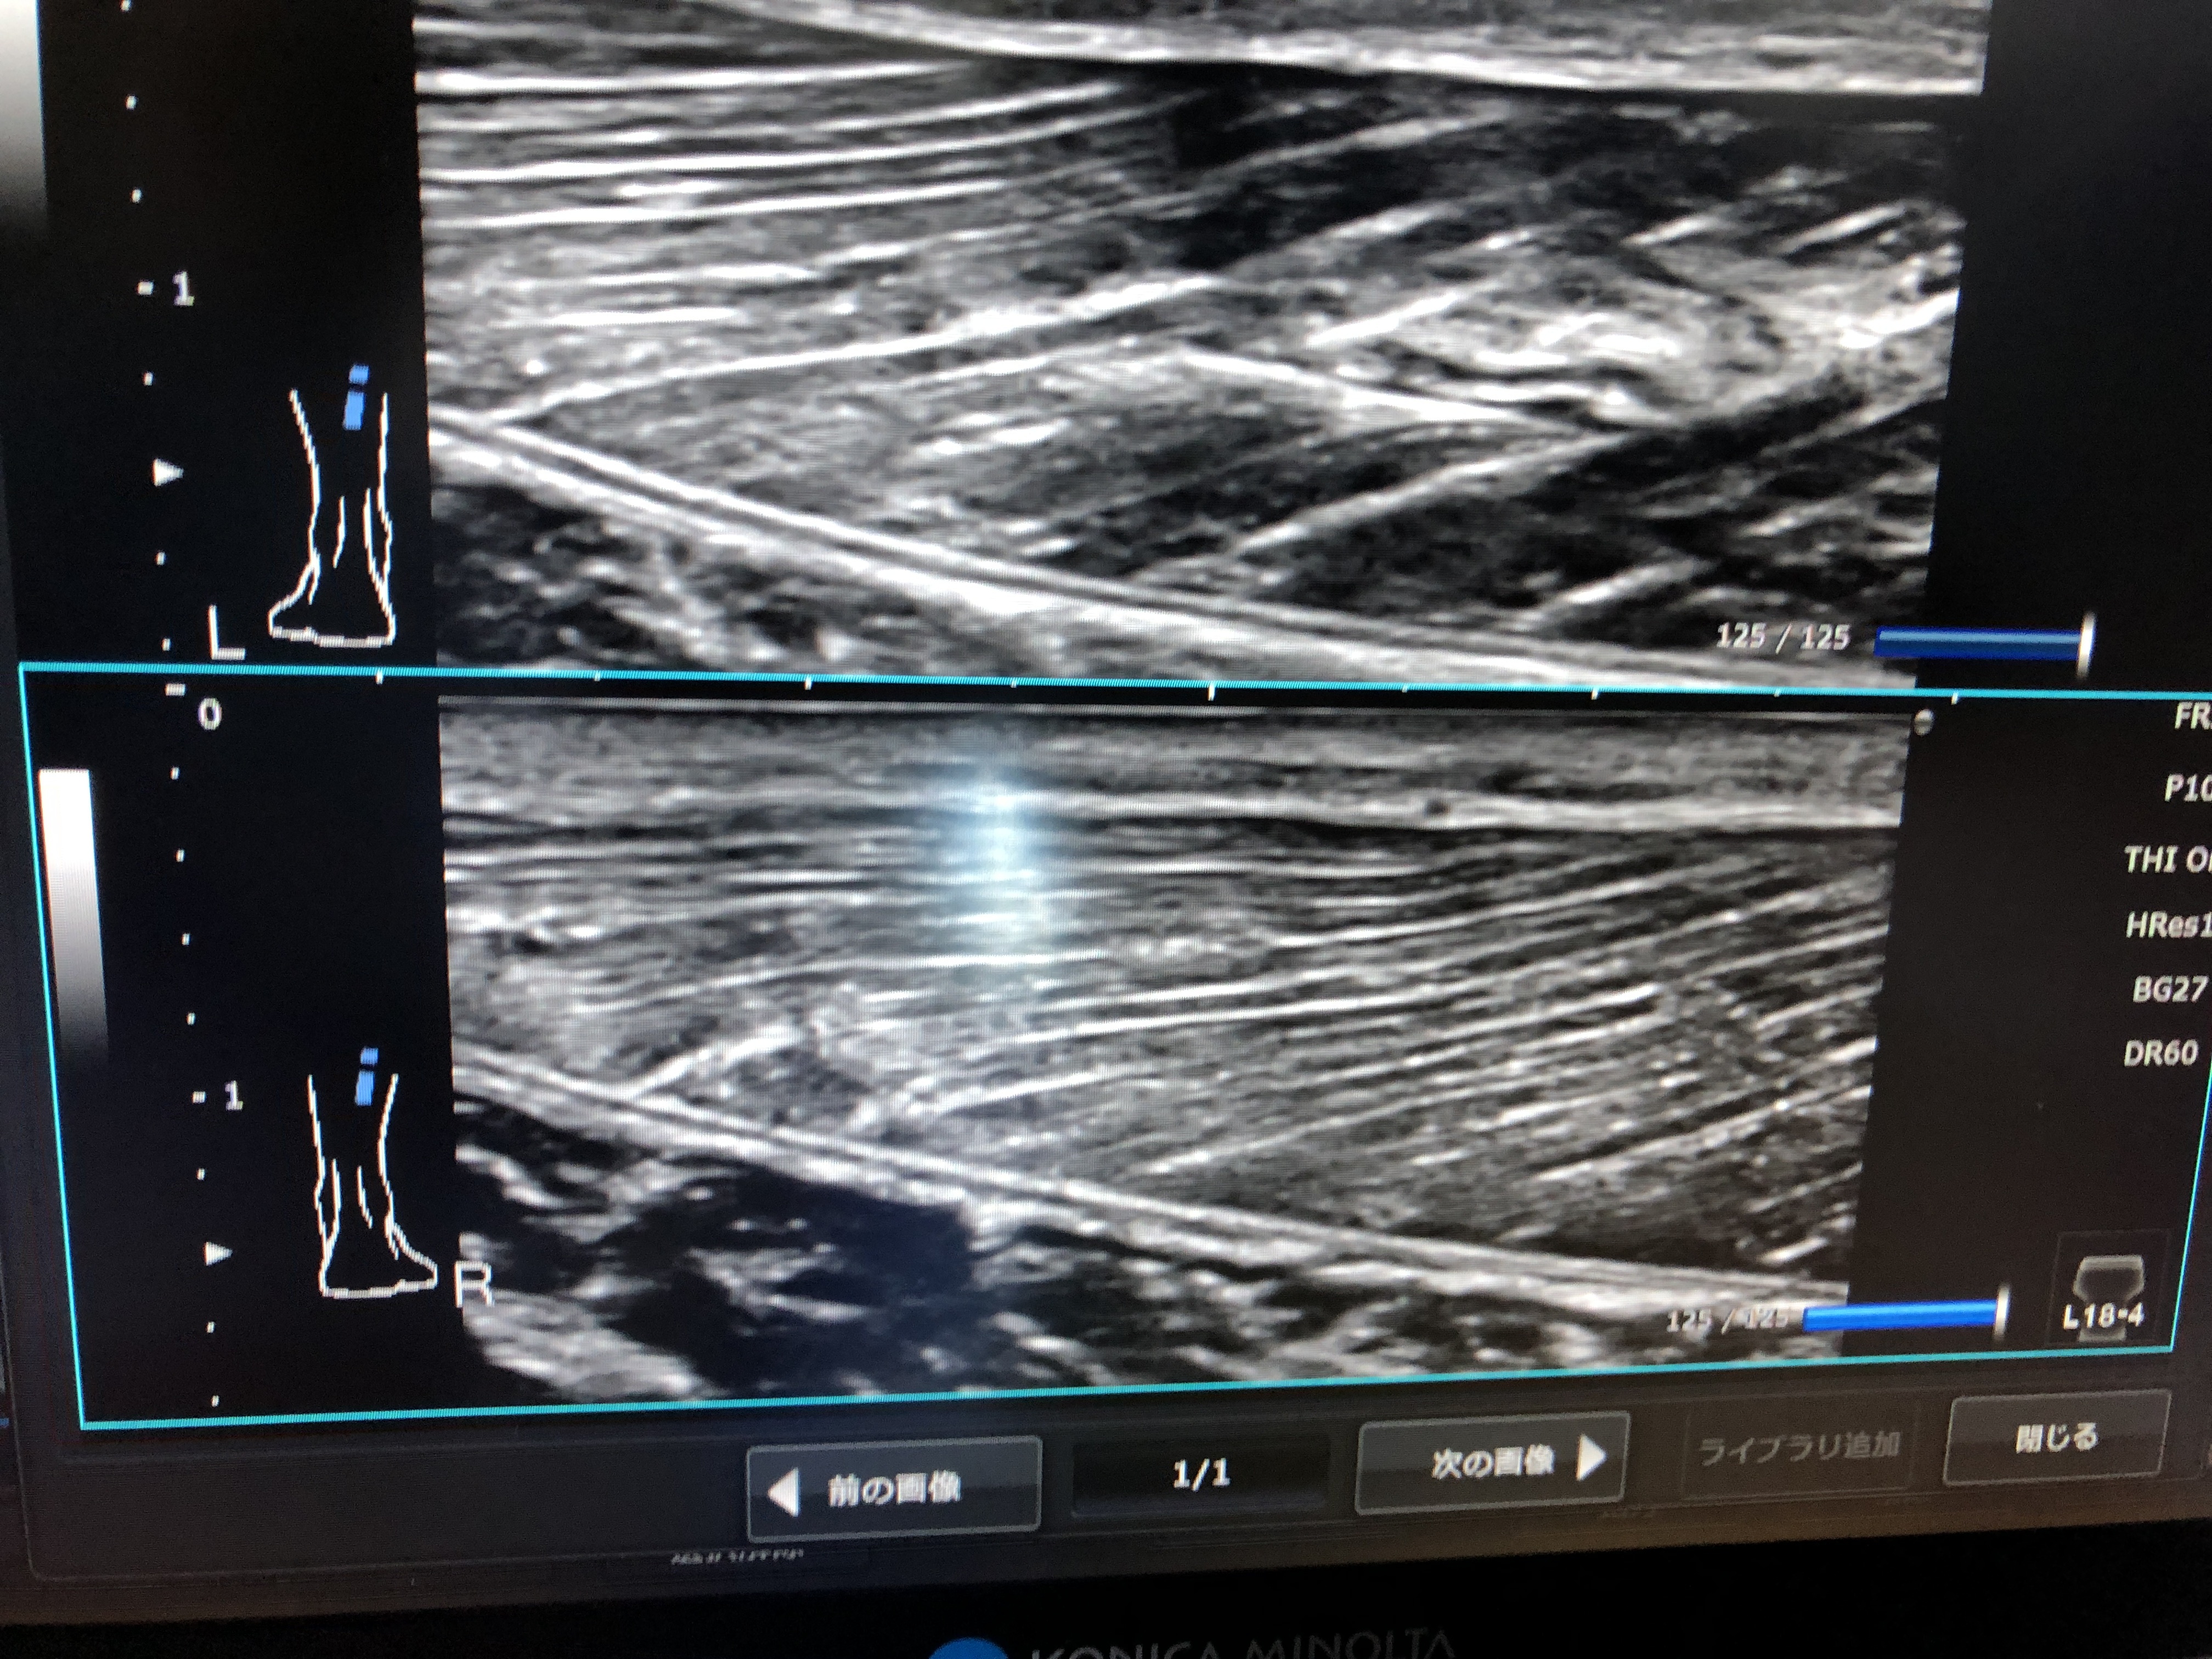

当院では、筋肉や骨の状態を見ることができる超音波エコーを導入しております。

ケガをしてしまった場所にあてることでどのような状態なのかを把握することができます!

左右の同じ場所に当たることで比較することが可能です!

こちらの症状では筋肉の繊維が痛んでおりますので、3週間〜1ヶ月くらいの症状と思います!